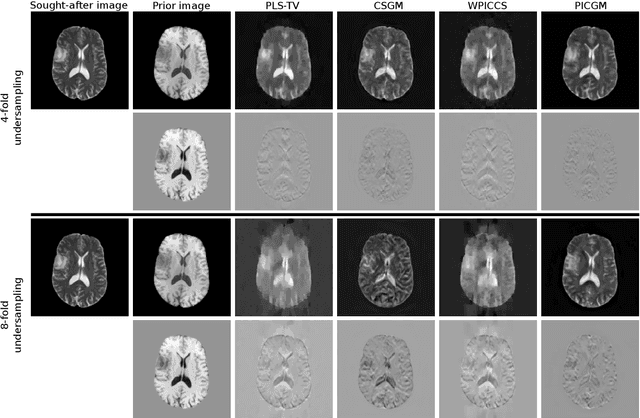

Computed medical imaging systems require a computational reconstruction procedure for image formation. In order to recover a useful estimate of the object to-be-imaged when the recorded measurements are incomplete, prior knowledge about the nature of object must be utilized. In order to improve the conditioning of an ill-posed imaging inverse problem, deep learning approaches are being actively investigated for better representing object priors and constraints. This work proposes to use a style-based generative adversarial network (StyleGAN) to constrain an image reconstruction problem in the case where additional information in the form of a prior image of the sought-after object is available. An optimization problem is formulated in the intermediate latent-space of a StyleGAN, that is disentangled with respect to meaningful image attributes or "styles", such as the contrast used in magnetic resonance imaging (MRI). Discrepancy between the sought-after and prior images is measured in the disentangled latent-space, and is used to regularize the inverse problem in the form of constraints on specific styles of the disentangled latent-space. A stylized numerical study inspired by MR imaging is designed, where the sought-after and the prior image are structurally similar, but belong to different contrast mechanisms. The presented numerical studies demonstrate the superiority of the proposed approach as compared to classical approaches in the form of traditional metrics.